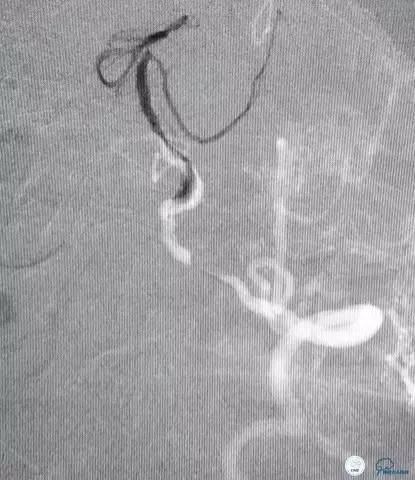

术前DSA(图7-8):右侧椎动脉颅外段纤细,非优势供血,颅内段以远未见显影;左侧椎动脉颅内段PICA动脉以远次全闭塞(狭窄率约为95%以上),基底动脉缓慢浅淡显影,双侧大脑后动脉未见显影。左侧前循环通过后交通动脉向后循环部分区域代偿供血。

图7

图8